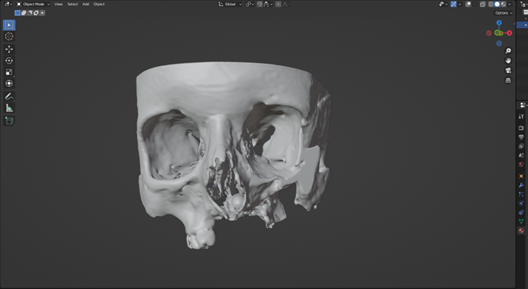

The patient suffered significant trauma to the right side of her face, including partial loss of her right eye, a laceration to the upper jaw, and damage to the orbital floor. Through detailed CT scan analysis and the use of Blender—a professional-grade 3D design software—the medical engineering team reconstructed the affected facial structure and designed a highly accurate, patient-specific implant to restore both functionality and appearance.

This personalized implant serves as a precise anatomical replacement for the missing bone structure and represents a major step toward 3D printing it in a biocompatible material such as titanium. The goal is not only to restore facial aesthetics but also to support improved medical outcomes and quality of life.